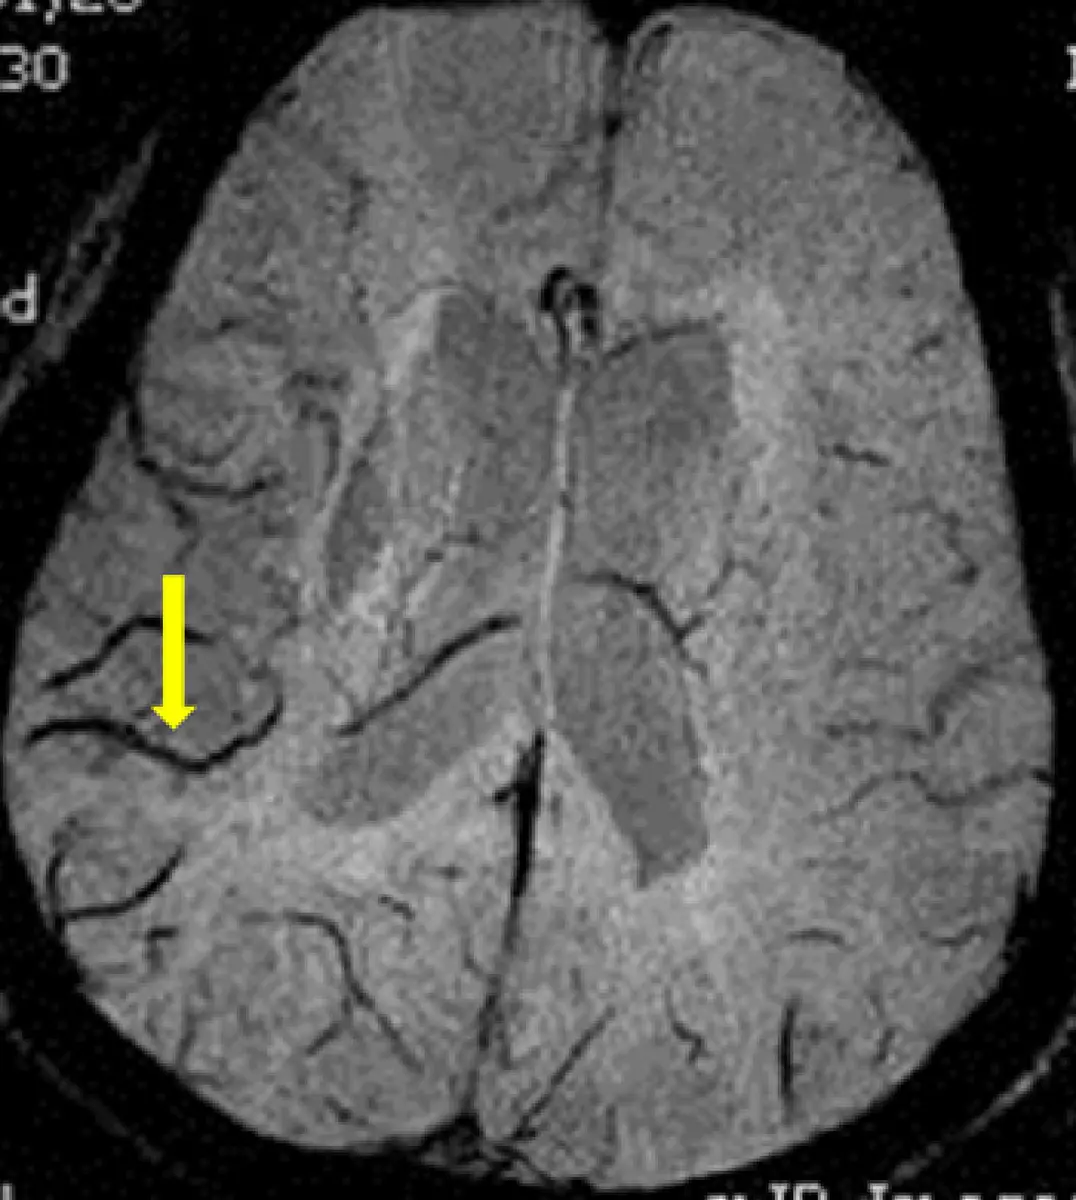

附圖箭號所指黑色條狀物最可能是下列那一項?

本題考查腦部 MRI 影像判讀,特別是磁感受性加權影像(susceptibility weighted imaging, SWI)或 T2* 梯度回波(T2* gradient recalled echo, GRE)序列上,腦皮質靜脈(cortical vein)的正常影像表現。腦皮質靜脈因含有去氧血紅素(deoxyhemoglobin)而呈現顯著低訊號(hypointense)的黑色條狀或蜿蜒狀結構,此即所謂的「流空效應(flow void)」及磁感受性效應(magnetic susceptibility effect, MSE)的綜合表現。

本圖為腦部 MRI 軸切面(axial plane),影像特性符合 SWI(磁感受性加權影像)或 T2*GRE 序列的表現:

- 整體影像背景為灰白色腦實質,腦溝、腦迴清晰可見

- 影像中可見多條分布於大腦皮質表面的蜿蜒黑色條狀結構,沿腦溝走行,形態彎曲,符合皮質靜脈的解剖走行

- 黃色箭號指向左側大腦半球皮質表面的一條清晰黑色條狀蜿蜒結構,外觀為細長、彎曲的帶狀低訊號影

- 此黑色條狀結構不具有佔位效應(mass effect),無周圍水腫,形態規則連續,符合正常腦皮質靜脈在 SWI/T2*GRE 上的正常表現